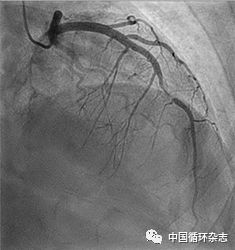

患者的治疗转折点是冠脉造影,造影显示左前降支长这样:

根据流行病学特点和冠脉造影结果,患者最终被确诊为自发性冠脉夹层,给予β受体阻滞剂和阿司匹林继续治疗。

自发性冠脉夹层的造影可能有3种表现:

1型,冠脉形成多个可见的腔,动脉壁会沾染对比剂;

2型,冠脉弥漫性狭窄,血管狭窄的其中一端口径变化明显;

3型,冠脉局部或管状狭窄,与动脉粥样硬化相似。

其中2型最常见,3型最难区分。此例患者的造影表现为2型。